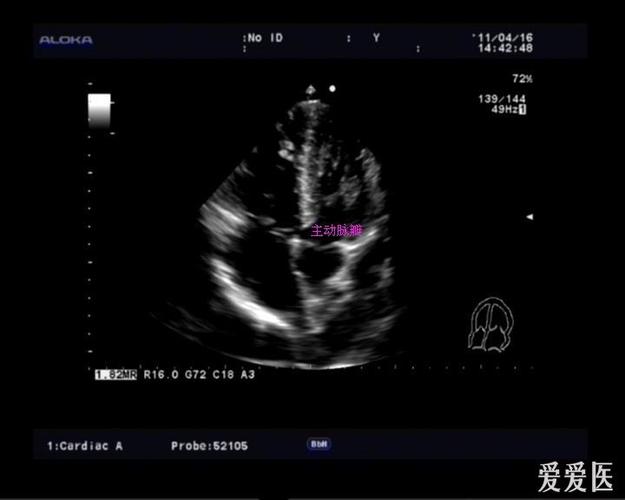

点击查看大图 图2 心尖四腔心切面超声图像 图3 心尖五腔心切面超声

心尖五腔心切面.jpg